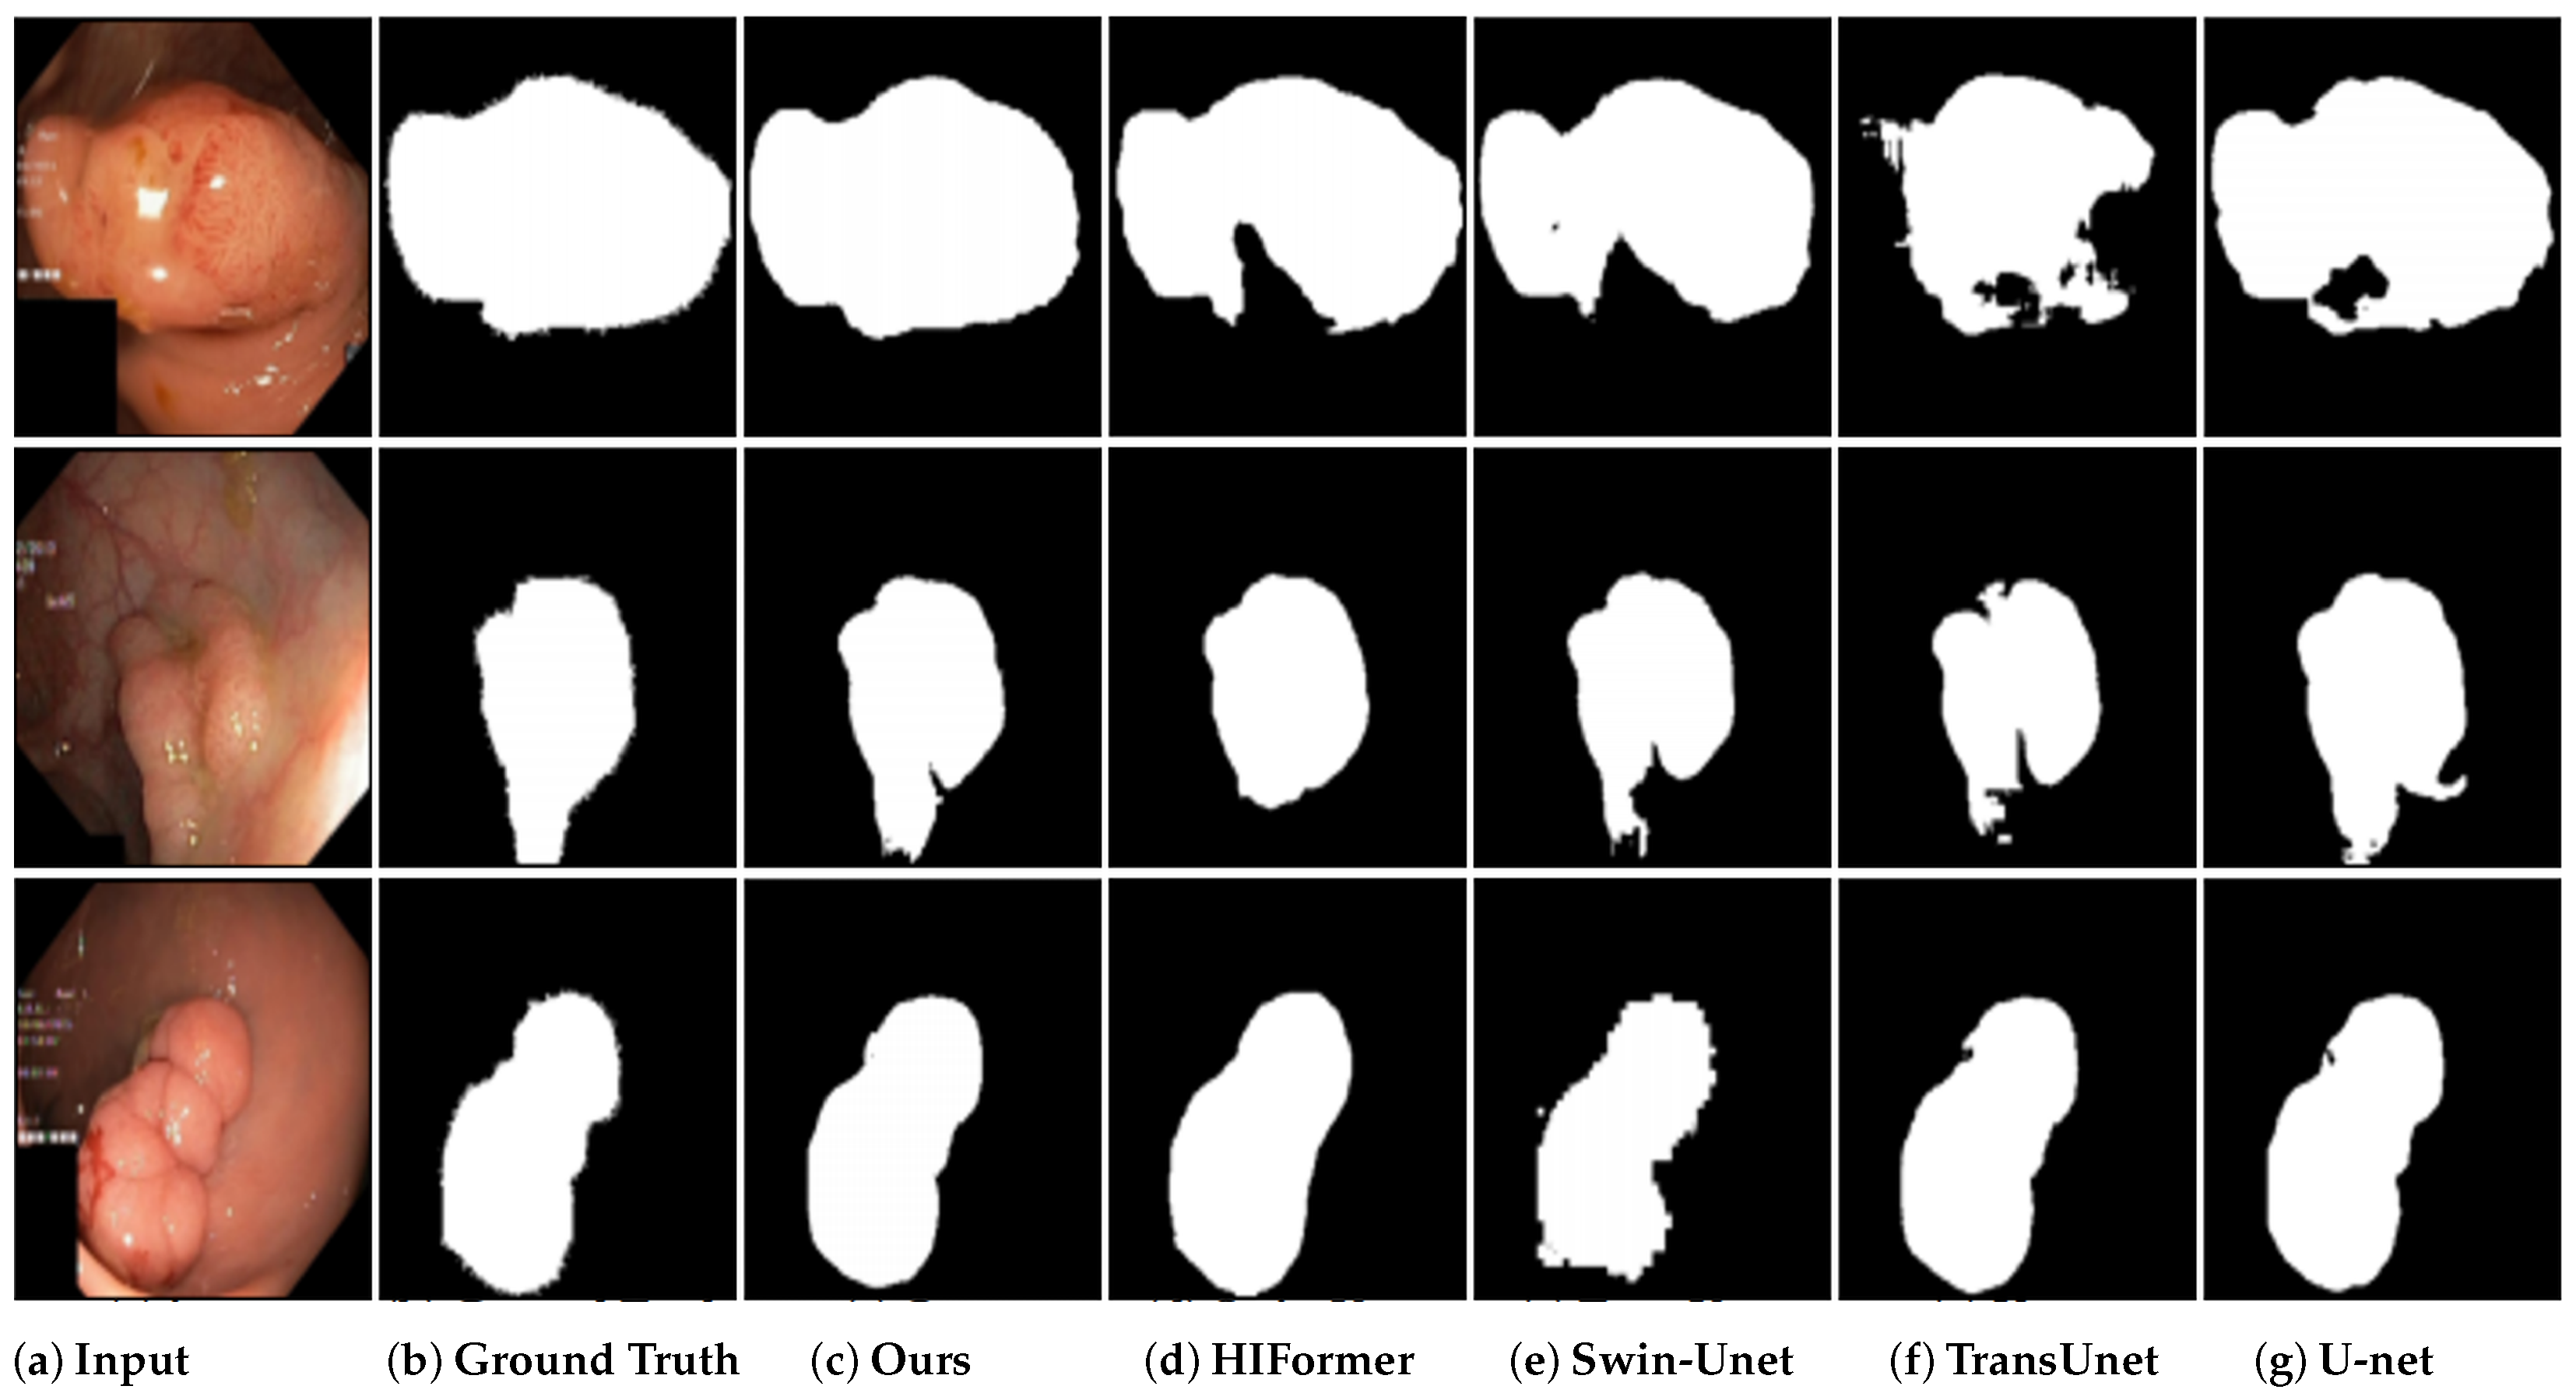

4.5. Results on ACDC Segmentation

4.6. Results on Kvasir-SEG Segmentation